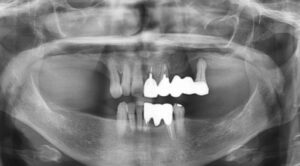

今日のインプラントは、右下の奥歯に2本でした。本来なら入れ歯になる所ですが、入れなくて済んで良かったと感動されて帰りました。ゴールデンウィークに間に合ってよかったですね。 レントゲンで見るとインプラントから歯に移行する立ち上がりのラインもき […] 本文を読む